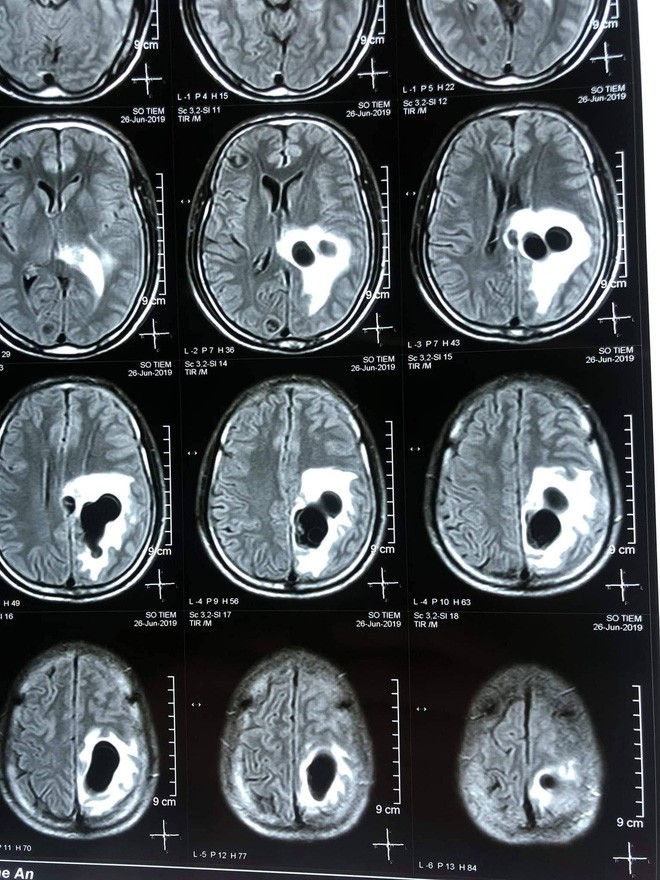

04/07/2019 21:52Đau đầu đi cấp cứu phát hiện 5 ổ sán lớn nằm trong não người đàn ông ăn tiết canh

Ngày 3/7, Bệnh viện hữu nghị đa khoa Nghệ An cho biết, bệnh viện này vừa phẫu thuật vét 5 ổ sán trong đầu một bệnh nhân nam do ăn tiết canh, ăn đồ sống.

Qua thăm khám và chụp CT não cho thấy có 5 ổ sán nằm rải rác trong não bệnh nhân S.. Trong đó có một ổ sán lớn trên đỉnh của bệnh nhân gây phù não. Bệnh nhân sau đó được chỉ định can thiệp ngoại khoa để lấy được trọn vẹn ổ nang sán khỏi não.

Ca mổ thành công, bệnh nhân S. hồi phục, tỉnh táo, không liệt, đi lại và sinh hoạt bình thường.

Các bác sỹ tại bệnh viện cho biết, kén sán não là bệnh nhiễm trùng hệ thần kinh do ấu trùng sán sống ký sinh ở người gây ra. Bệnh thường gặp ở người dân ăn thịt lợn chưa nấu chín, ăn tiết canh, ăn gỏi sống.